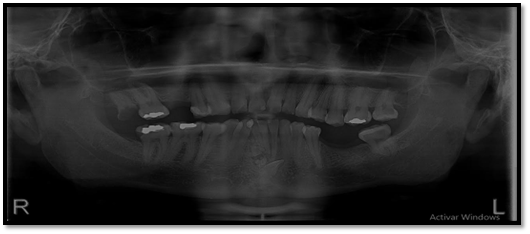

El órgano dentario retenido tiene una dirección mesioangular, sobrepasando la corona la mitad de la línea media. En íntima relación se encuentra las raíces de los órganos dentarios 4.1; 3.1; 3.2 con los dentículos y adicionándose con la relación del órgano dentario retenido esta la raíz del órgano dentario.

Imagen 3. Radiograficas Peiapical.